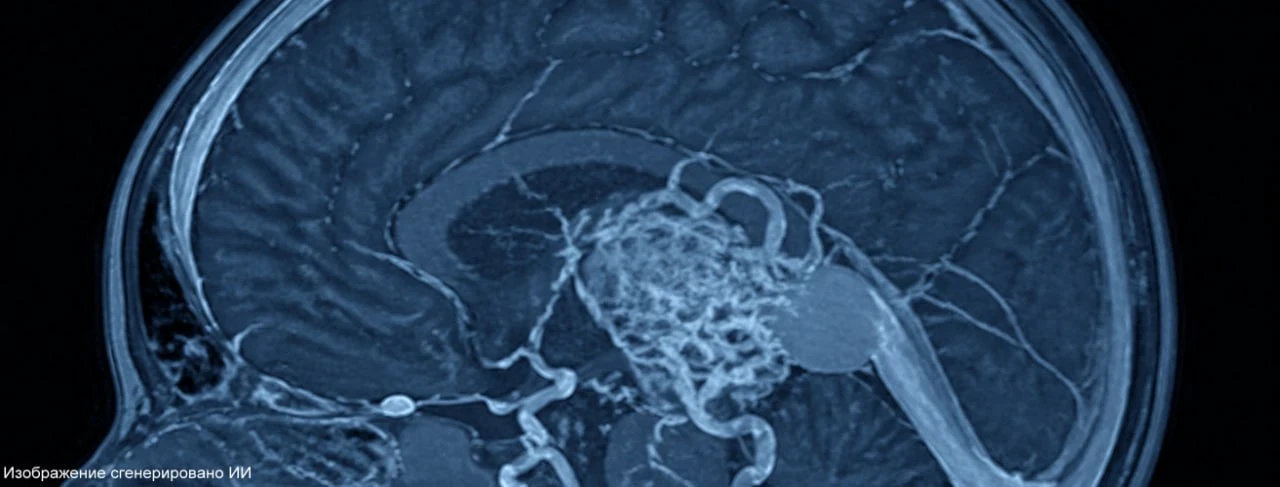

У новорожденного была диагностирована опасная патология мозга — артериовенозная мальформация вены Галена, сообщили в пресс-службе Педиатрического университета. Без операционного вмешательства прогноз крайне неблагоприятный: сердце не справляется и в любой момент может произойти разрыв хрупких сосудов с кровоизлиянием в мозг.

26 апреля питерские врачи успешно провели сложную операцию, которая была необходима малышу — эндоваскулярное вмешательство.